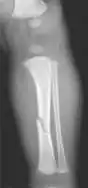

The material factual allegations of the amended complaint are as follows. Plaintiff was born on May 14, 1970. On repeated occasions during the first year of her life she was severely beaten by her mother and the latter's common law husband, one Reyes. On April 26, 1971, when the plaintiff was eleven months old, her mother took her to the San Jose Hospital for examination, diagnosis, and treatment. The attending physician was defendant Dr. Flood, acting on his own behalf and as agent of the defendant San Jose Hospital. At the time, the plaintiff was suffering from a comminuted spiral fracture of the right tibia and fibula, which gave the appearance of having been caused by a twisting force. Plaintiff's mother had no explanation for this injury. Plaintiff had bruises over her entire body. In addition, she had a non-depressed linear skull fracture which was then in the process of healing. Plaintiff demonstrated fear and apprehension when approached. Inasmuch as all plaintiff's injuries gave the appearance of having been intentionally inflicted by other persons, she exhibited the medical condition known as the battered child syndrome.

It is alleged that proper diagnosis of plaintiff's condition would have included taking X-rays of her entire skeletal structure, and that such procedure would have revealed the fracture of her skull. Defendants negligently failed to take such X-rays, and thereby negligently failed to diagnose her true condition. It is further alleged that proper medical treatment of plaintiff's battered child syndrome would have included reporting her injuries to local law enforcement authorities or juvenile probation department. Such a report would have resulted in an investigation by the concerned agencies, followed by a placement of plaintiff in protective custody until her safety was assured. Defendants negligently failed to make such report.

For example, the leading article by Kempe et al., op. cit., supra,[10] states that "A physician needs to have a high initial level of suspicion of the diagnosis of the battered-child syndrome in instances of subdural hematoma, multiple unexplained fractures at different stages of healing, failure to thrive, when soft tissue swelling or skin bruising are present, or in any other situation where the degree and type of injury is at variance with the history given regarding its occurrence . . . ." (Id., at p. 20.) Of the different types of fractures exhibited, an arm or leg fracture caused by a twisting force is particularly significant because "The extremities are the 'handles' for rough handling" of the child by adults. (Id., at p. 22.) The article also contains numerous recommendations to conduct a "radiologic examination of the entire skeleton" for the purpose of confirming the diagnosis, explaining that "To the informed physician, the bones tell a story the child is too young or too frightened to tell." (Id., at p. 18.) Finally, on the subject of management of the case it is repeatedly emphasized that the physician "should report possible willful trauma to the police department or any special children's protective service that operates in his community" (id., at p. 23) in order to forestall further injury to the child: "All too often, despite the apparent cooperativeness of the parents and their apparent desire to have the child with them, the child returns to his home only to be assaulted again and suffer permanent brain damage or death." (Id., at p. 24.)